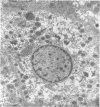

Type I mucopolysaccharidosis was diagnosed in a fetus by assay of the glycosaminoglycans of the amniotic liquor. Results are presented of biochemical and ultrastructural studies on the 18-week abortus. The evidence suggests that the liver is more severely affected than the central nervous system at this stage of gestation, and this finding agrees with the recent demonstration of the underlying enzyme defect of this disorder, with the corollary that many biochemical abnormalities previously noted in gargoylism must be pleiotropic effects of the mutant genotype.